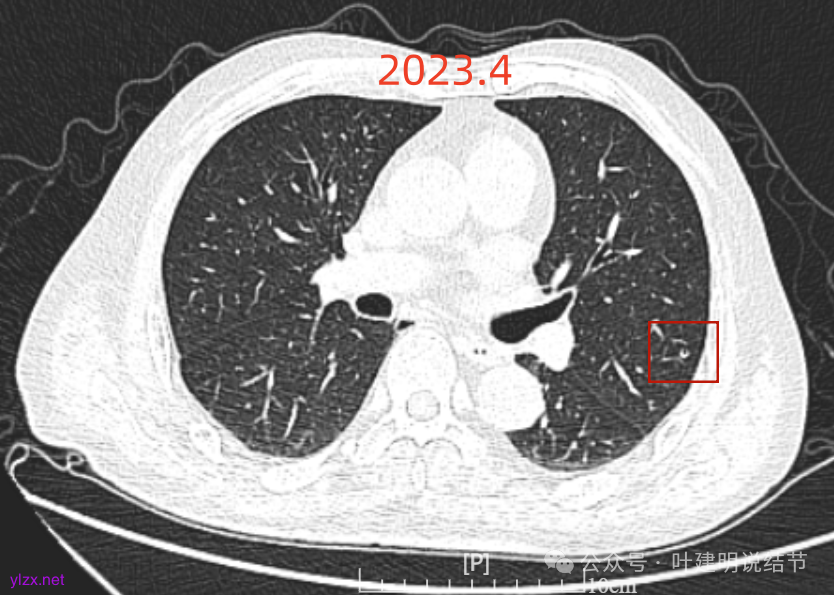

再看2023年时的影像主要层面:

左上当时也有,但囊壁明显是较现在薄的。

左肺上叶红色这处是囊腔型病灶,囊壁略不均,似有微小血管进入囊壁,对比2023年4月整个囊腔来讲有扩大,需要考虑囊腔型肺癌的可能性大。右侧蓝色的并不是典型囊腔型肺癌的表现,再加上两肺绿色这些慢支肺气肿与肺大泡的影像,右侧的就更加不确切,至少近期不能够考虑右侧也要开刀的事情。其实左侧的主病灶相对于其他表现更典型的囊腔型肺癌来说,由于囊壁密度偏高,也不是百分百必定是肺癌。我的想法还是先等脑梗情况稳定,并且间隔4~6个月复查病灶再有进展在考虑单孔胸腔镜下局部切除就可以。淋巴结可以考虑采样,但一般不至于阳性。破是不会切破的。消融不建议,囊腔灶更难通过穿刺获得病理依据,况且东西在边上,能局部楔切,当然首选手术。意见供参考!